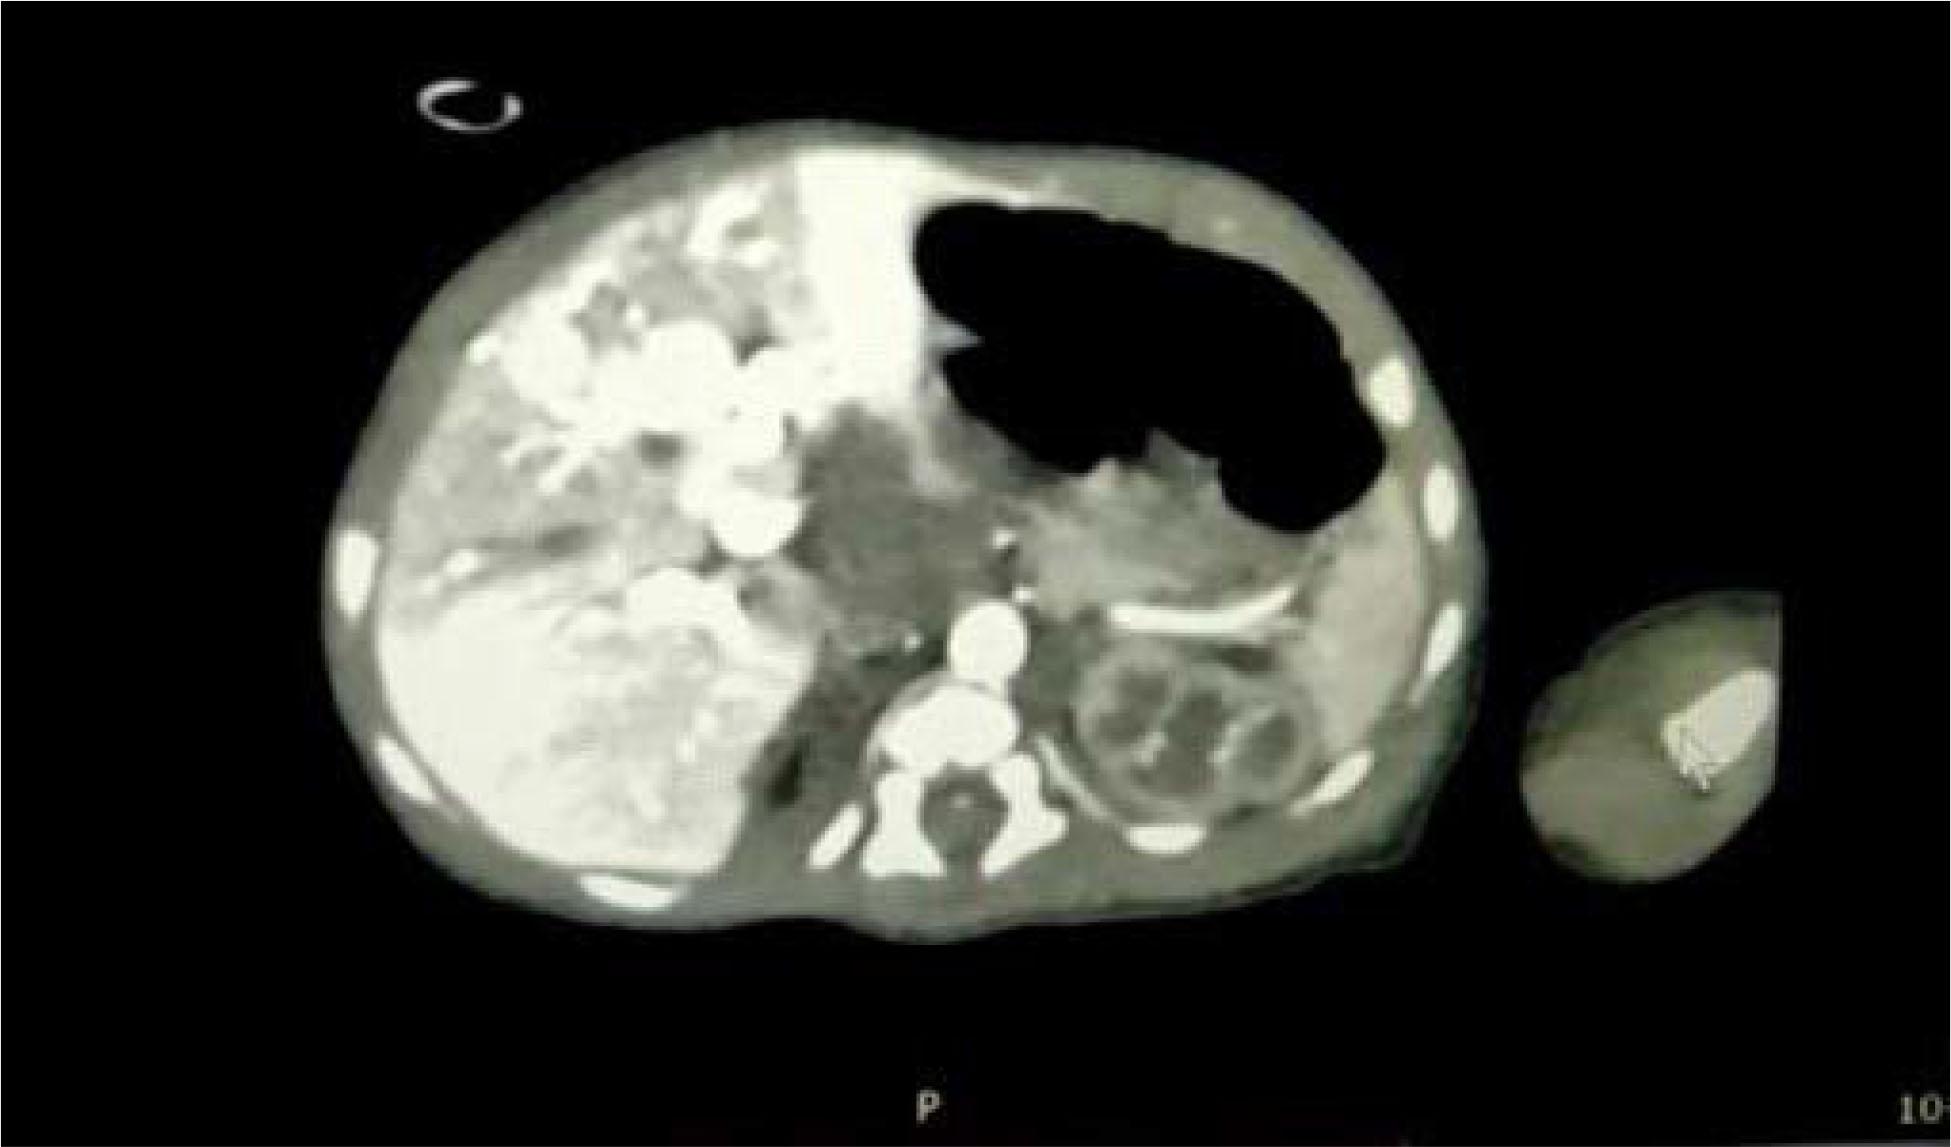

Figure 2

Contrast-enhanced CT scan showing mild enhancement or attenuation similar to that of adjacent parenchyma on delayed images and dilated celiac trunk.